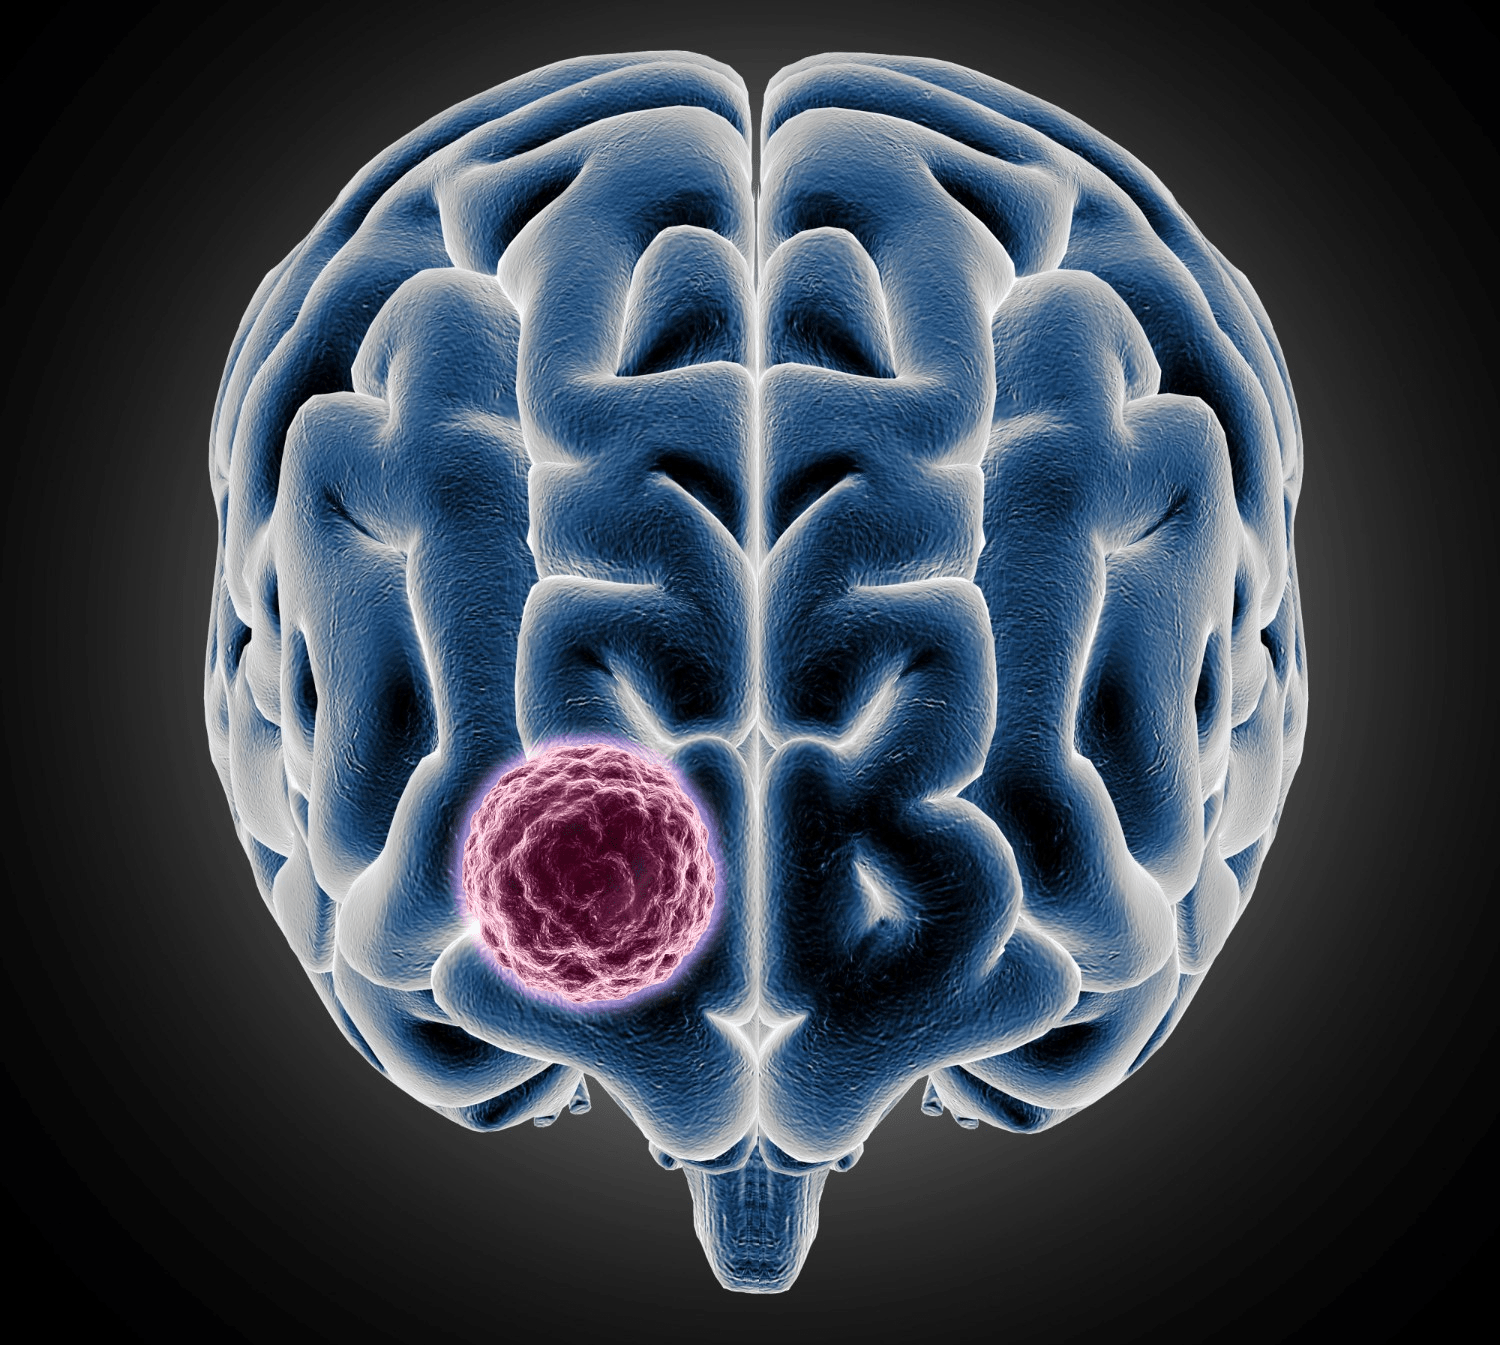

Why Early Signals Matter More Than You Think

Your brain is incredibly delicate. Even tiny changes in pressure, swelling or nerve signals can cause unusual sensations throughout your body. These sensations might appear harmless at first.

This is why early symptoms are often confusing. They’re subtle. They come and go. They resemble everyday issues like stress or poor sleep. Yet noticing them early may encourage people to seek evaluation sooner.

And while these signs do not mean you have a brain tumor, they could be your body’s way of saying, “pay attention.” That’s why recognizing patterns matters.